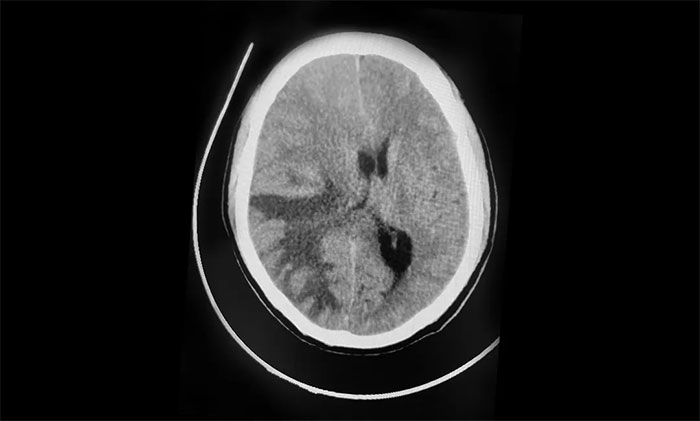

1月5日早晨,張先生反復(fù)出現(xiàn)頭痛、嘔吐。腫瘤科、放療科、神經(jīng)外科6B病區(qū)專家緊急會診,并急查頭顱CT。影像顯示,右側(cè)額頂葉、枕葉見多枚大小不等團塊狀等密度影,最大者約4.2*4.8cm,周圍大片低密度水腫。右側(cè)腦室受壓變窄,中線結(jié)構(gòu)向左側(cè)偏移超過1.0cm。

▲ 中線結(jié)構(gòu)向左側(cè)偏移

“手術(shù)宜早不宜遲,越早越好!”潘仁龍主任、吳治群博士分析指出。結(jié)合影像表現(xiàn),共發(fā)現(xiàn)有三處腫瘤,并伴嚴重水腫,腦組織向腦干處移位,腦干受壓明顯,顱內(nèi)壓急劇升高,患者意識狀態(tài)逐漸惡化,已經(jīng)處于腦疝臨界狀態(tài)。